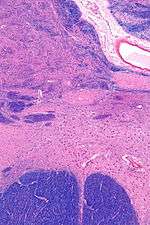

MRI showing a coronal plane of the head with marks showing the location of the substantia innominata, the region in which the nucleus basalis is found. | |

The NBM is inferior to the globus pallidus and within an area known as the substantia innominata. The NBM is immediately inferior to the anterior commissure and superior and lateral to the anterior portion of the hypothalamus.